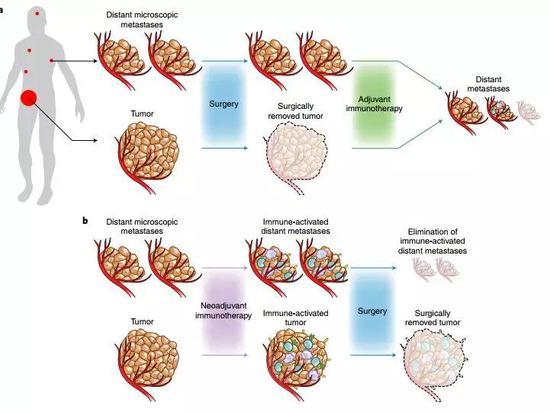

怎么解决这样的困境呢?医学界先后提出了两种套路,一种是在手术后进行的放化疗,也就是辅助治疗;而另外一种,则是把放化疗的时间挪到手术前,就是即将谈到的新辅助治疗了。

从理论上来说,新辅助治疗可能给患者带来的获益和优势包括:

1、在手术前缩小肿瘤,降低手术难度,甚至给原本无法手术的患者手术的机会

2、提前清除掉那些肉眼不可见,但已经存在的微小转移灶,降低复发风险

3、手术前肿瘤部位的血供保持比较完整,治疗药物可以更有效的到达肿瘤处

4、患者在手术前的身体状态相对较好,能更好地耐受放化疗[2]

免疫疗法,能不能再次超越放化疗呢?从理论上来说,免疫新辅助治疗也有不少优势,比如手术前患者的免疫系统更加完整,只是被肿瘤操纵,进入了明显的免疫抑制状态[4]。这样的话,PD-1/L1抑制剂们就不容易放空枪。

免疫治疗还可以利用手术前肿瘤体积大,新抗原多的特点,充分增强体内抗肿瘤免疫T细胞的活性,让它们分散到全身,清除微小的癌症转移灶,这比在辅助治疗时使用效果更好,优势已经在临床前期的动物实验中得到证实[5]。如果等到手术后再来做免疫治疗,随着免疫环境的变化,这些好处可能就减弱了。

从科研角度来说,免疫新辅助治疗之后再做手术,还能把手术中切除的肿瘤组织,作为进一步抗癌研究的材料。让免疫疗法担任新辅助治疗的角色,和手术可以说是强强联手,在乳腺癌和黑色素瘤的治疗中都已经有了成功的先例。